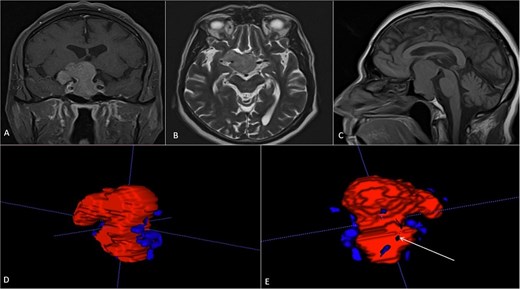

A 68-year-old male patient with an 8-year history of gradual loss of visual acuity. An MRI study was performed with the following sequences: T1, T2, and T1 with contrast. When performing the three-dimensional segmentation, we realized the intimate relationship that the dorsum of the tumor had with the basilar artery; its dolichoectatic course on the dorsal surface of the tumor was what we paid the most attention to and what made us plan a better transnasal approach and avoid the traction of the capsule mainly the dorsal region (Fig. 6).

(A, B and C) MRI of pituitary marcoadenoma in coronal, axial and sagittal sections, contrasted T1, T2, and T1 sequences. (D and E) Planimetric segmentation with 3D reconstruction of the basilar and carotid system. White arrow, relationship of the dorsum of the tumor with the basilar artery.